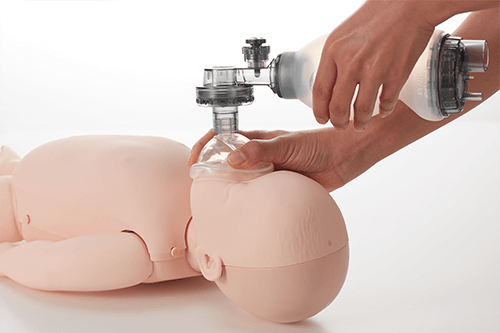

- The Brayden Baby has an open and interconnected mouth and nose which adds realism when ventilating.

- Brayden Baby has an easy to change ‘double filter’ connected to the lung when required.